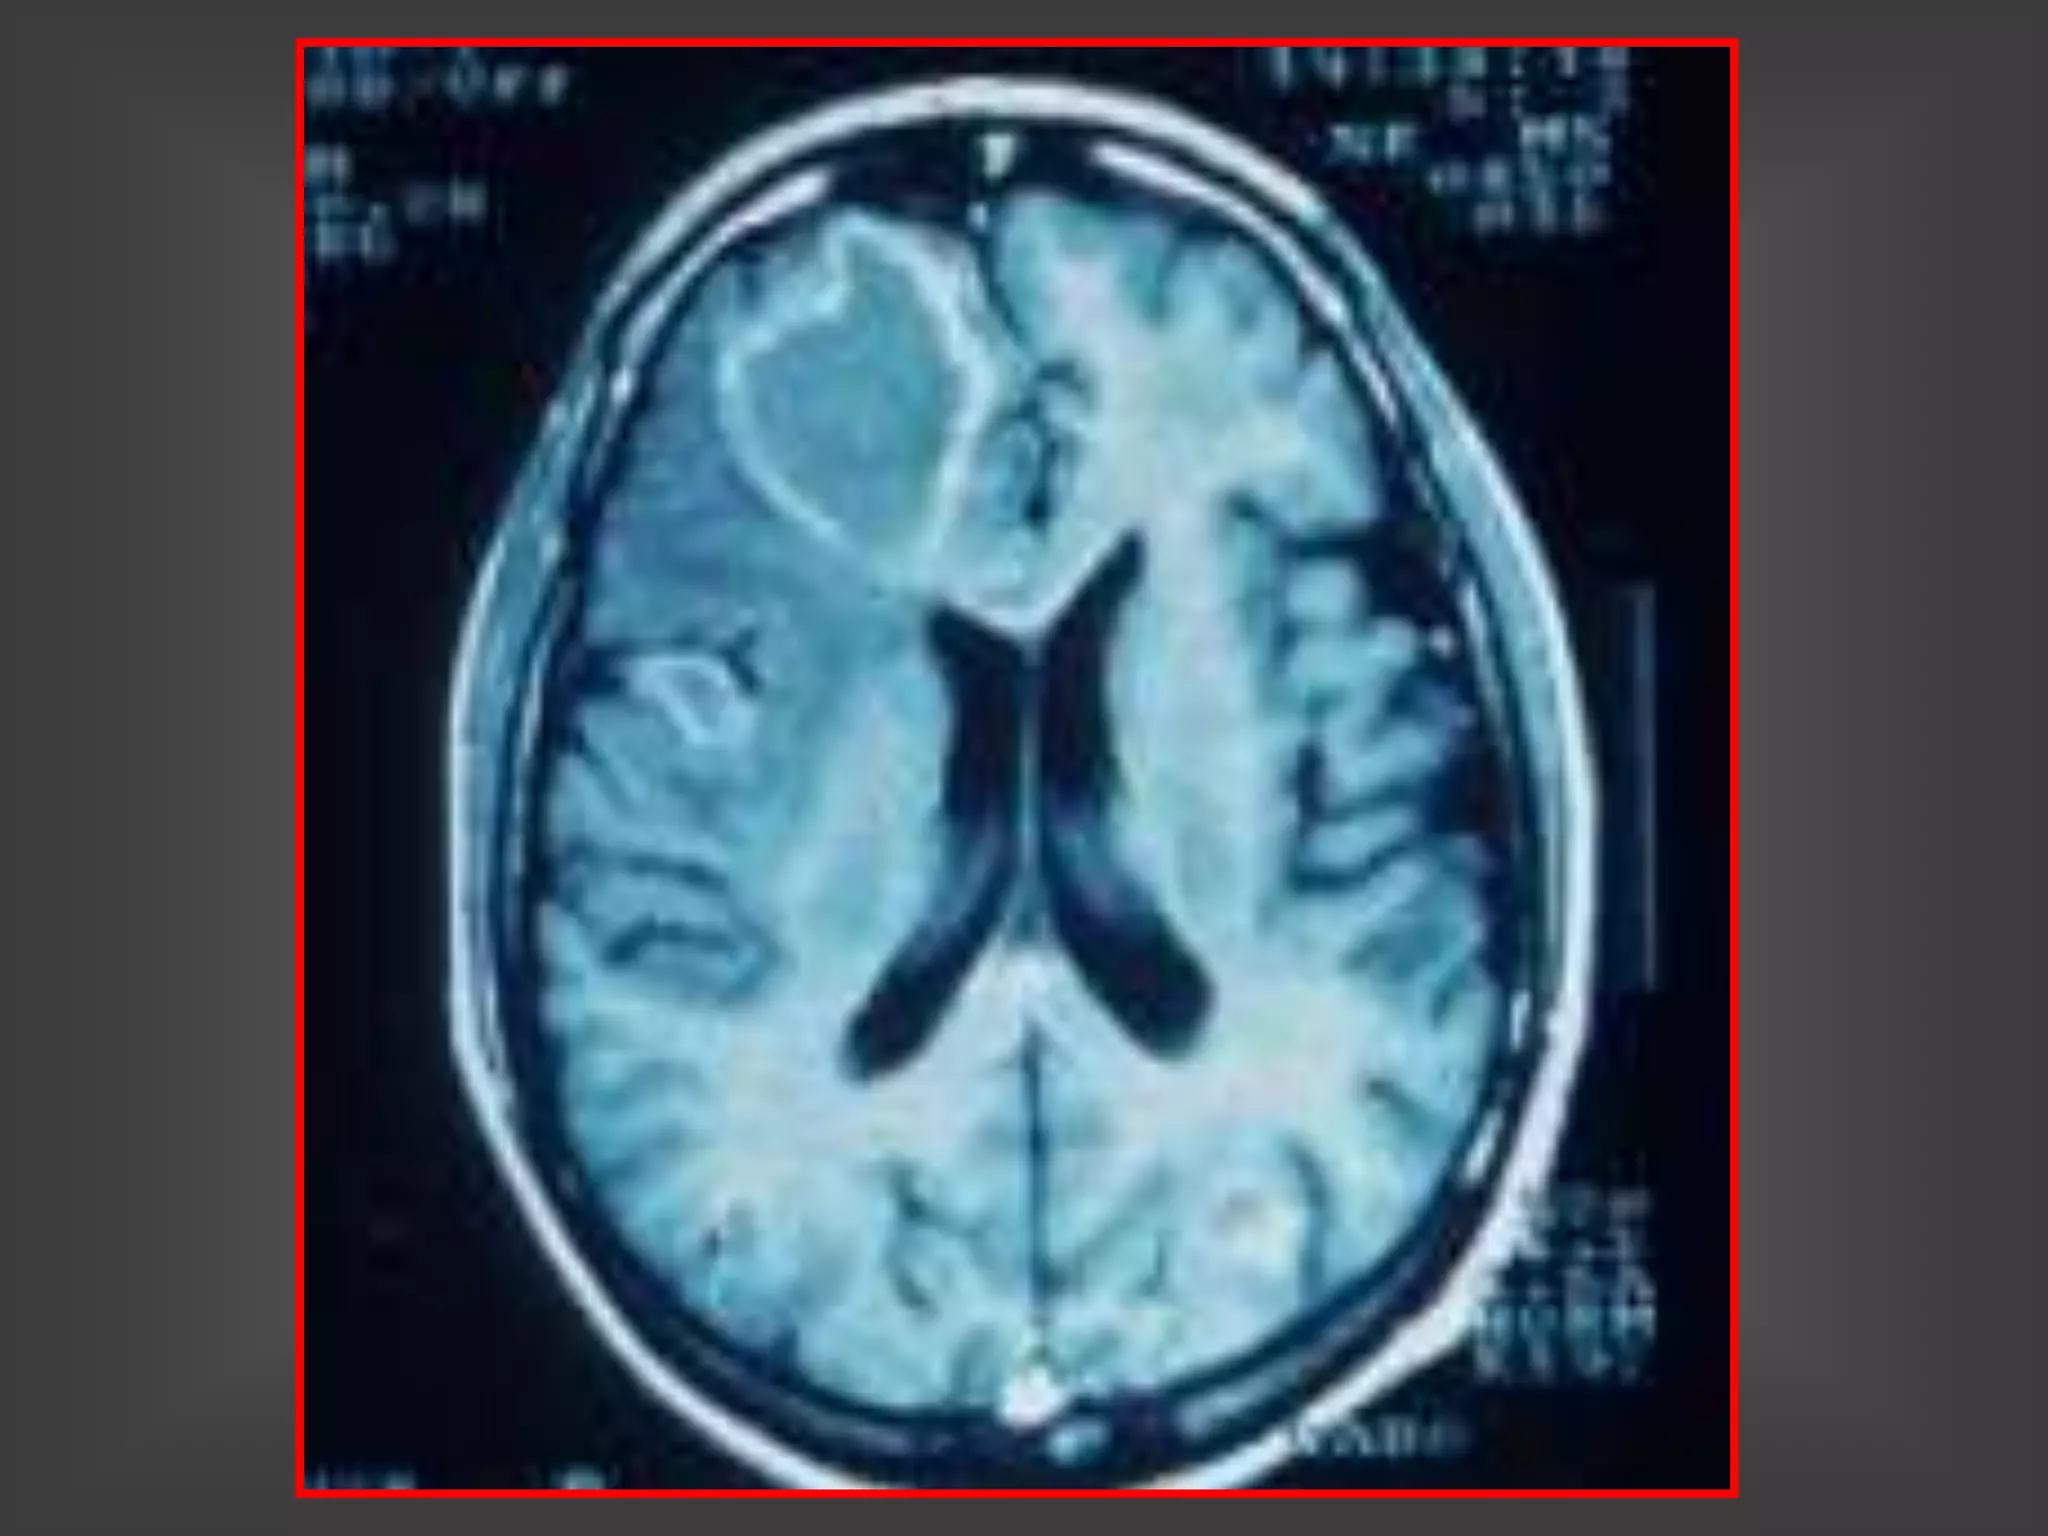

TOXOPLASMOSIS – RNM

LESIONES MÚLTIPLES

TOXOPLASMOSIS LESIONES

MÚLTIPLES EN RNM

TOXOPLASMOSIS CEREBRAL-SIDA

HALLAZGOS EN LAS NEUROIMÁGENES

1. Lesiones hipodensas con refuerzo en anillo y edema

perilesional

2. Lesiones hipodensas sin captación del contraste con

edema perilesional

3. Lesiones nodulares (toman el contraste en forma

homogénea) y edema perilesional

4. Edema cerebral localizado sin lesiones focales visibles

5. TAC sin lesiones y RNM con lesiones focales

1 y 3: 80% a 90% de las lesiones